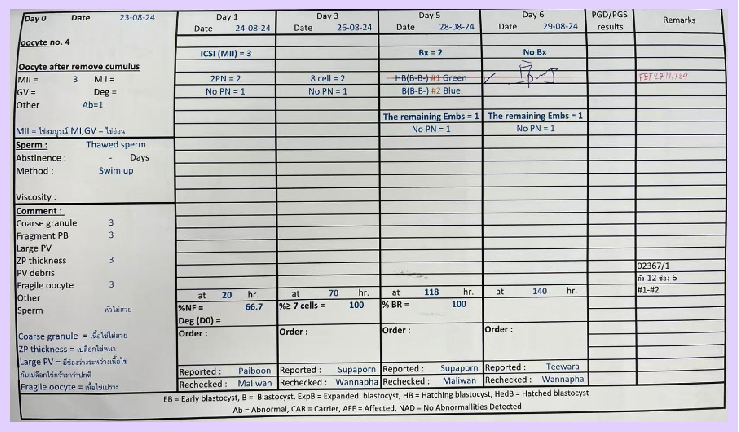

Embryo Development Results

- Oocytes Retrieved: 4

- Mature Eggs: 3

- Normally Fertilized: 2

- Day 3: 2 embryos with 8 cells each

- Day 5: 2 blastocysts formed and biopsied

- Chromosomal Screening: 1 normal embryo

▲ Ms. A’s blastocyst culture report

▲ Ms. A’s embryo screening report

Procedure: Transferred 1 normal embryo (Grade: HB, B-B-)